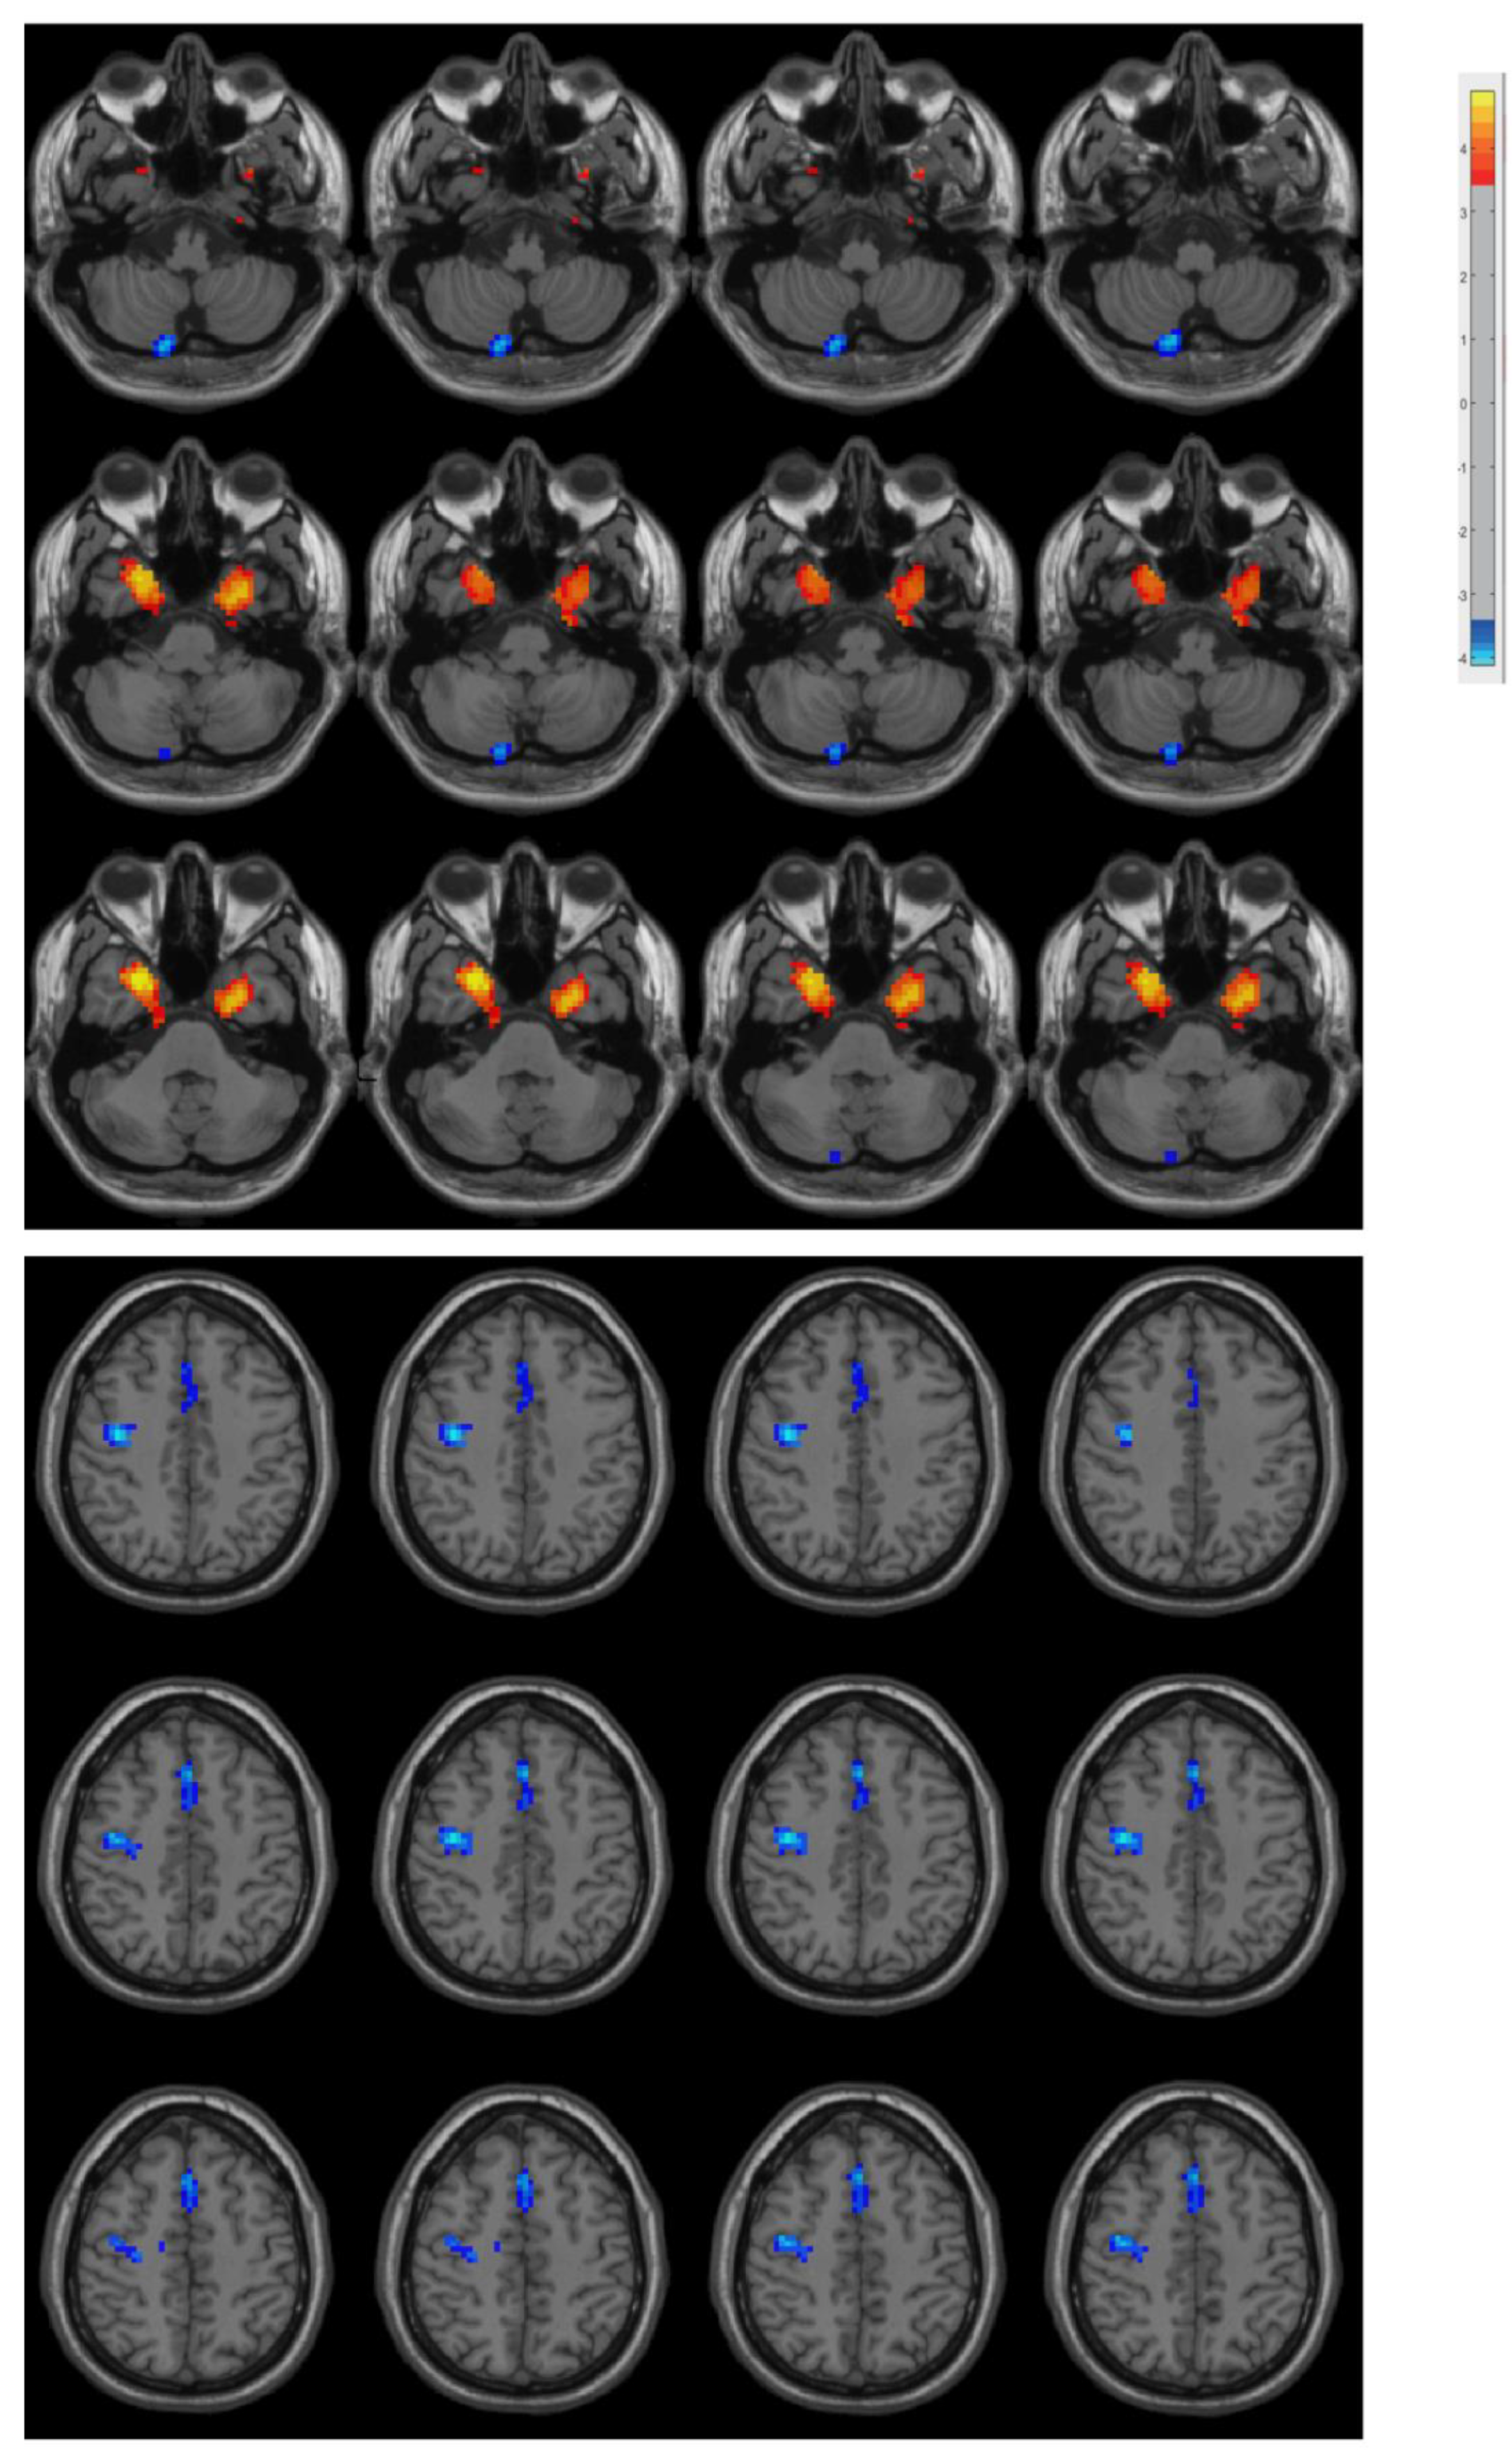

3.2. Difference in ReHo between PD Patients and Controls

| Region | Cluster Size (Voxel) | MNI (x, y, z) | t-Value |

|---|---|---|---|

| Right Posterior Cerebellar Lobe | 17 | (15, −81, −54) | −5.5695 |

| Left Medial Temporal Lobe | 52 | (−27, 0, −42) | 5.1186 |

| Right Medial Temporal Lobe | 74 | (27, 9, −39) | 5.4905 |

| Right Precentral Gyrus | 123 | (39, −9, 42) | −5.7469 |

| Supplementary Motor Area | 70 | (0, 24, 48) | −5.2007 |